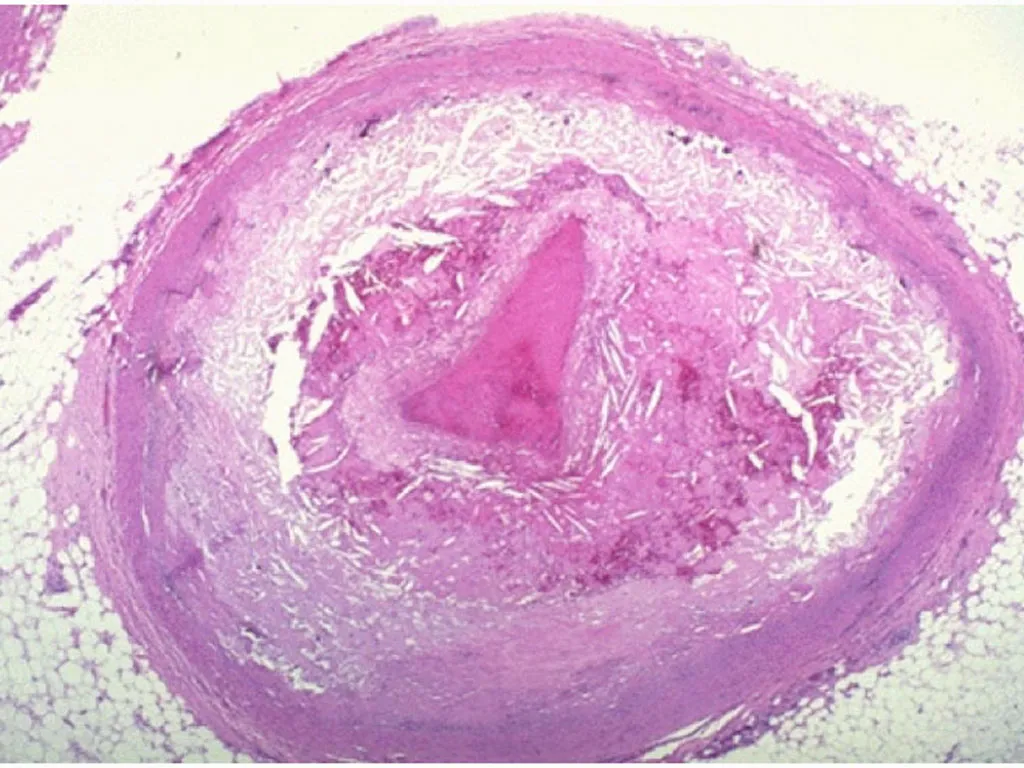

动脉粥样硬化

诊断:动脉粥样硬化性疾病的诊断通常是基于影像学表现和危险因素的结合,如果有的话,还需要病理标本。在影像学评估中,管腔狭窄的识别通常用于确定血栓事件的动脉粥样硬化病因,尽管事实上可见的动脉狭窄并不能很好地预测斑块易损性。这在缺血性卒中的评估中尤其相关——传统标准要求>50%狭窄才能诊断为大型动脉粥样硬化,但研究表明非狭窄斑块也可能破裂并导致卒中。因此,评估图像中是否存在非狭窄斑块和钙化也可能是有用的。